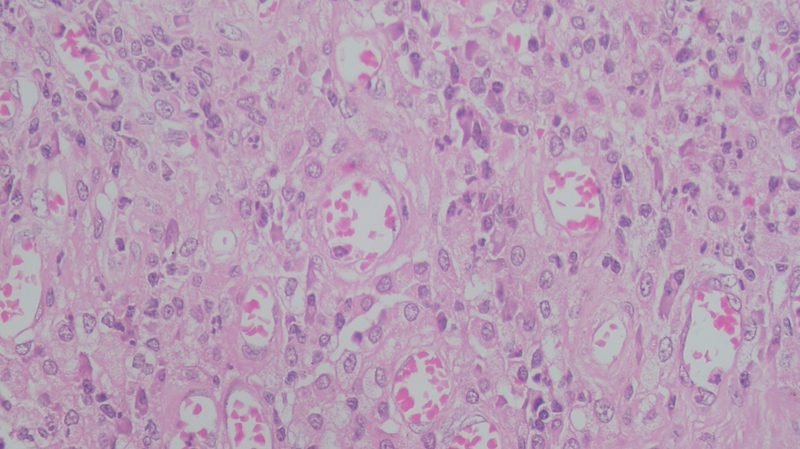

On microscopic examination, the cyst wall was seen to be comprising of fibrocollagenous tissue, infiltrated by sheets of foamy macrophages, lymphocytes, plasma cells, and neutrophils ([Fig. 1], [2], [3]). Proliferating blood vessels were noted. Few areas showed fibrosis with hemosiderin-laden macrophages. Endometrial glands or stroma was not seen. The features like atypia and dysplasia were characteristically absent. The appendix showed normal histomorphology with periappendiceal inflammation. CD68 immunohistochemistry confirmed the presence of foamy histiocytes ([Fig. 4], [5]), while pan-cytokeratin was negative. Diagnosis of xanthogranulomatous oophoritis was made, based on the histomorphological features.

| Fig. 3 The presence of large number of foamy histiocytes admixed with plasma cells, lymphocytes, and occasional neutrophils, is seen, which is pathognomonic feature of xanthogranulomatous oophoritis (hematoxylin and eosin staining; magnification 400x).

The gross appearance of the specimens may show cystic degeneration, foci of necrosis, and hemorrhage, in grossly enlarged ovary. The microscopic examination shows the presence of foamy histiocytes, along with a mixture of inflammatory cells like lymphocytes, plasma cells, and occasional neutrophils.[21] Foamy histiocytes, the so-called “xanthoma cells,” are histiocytes with abundant lipid-laden cytoplasm having a vacuolated appearance. These impart the yellowish color to the specimen, when seen on the gross examination. There is no cellular atypia, abnormal mitoses, or any other microscopic feature suggestive of malignancy.